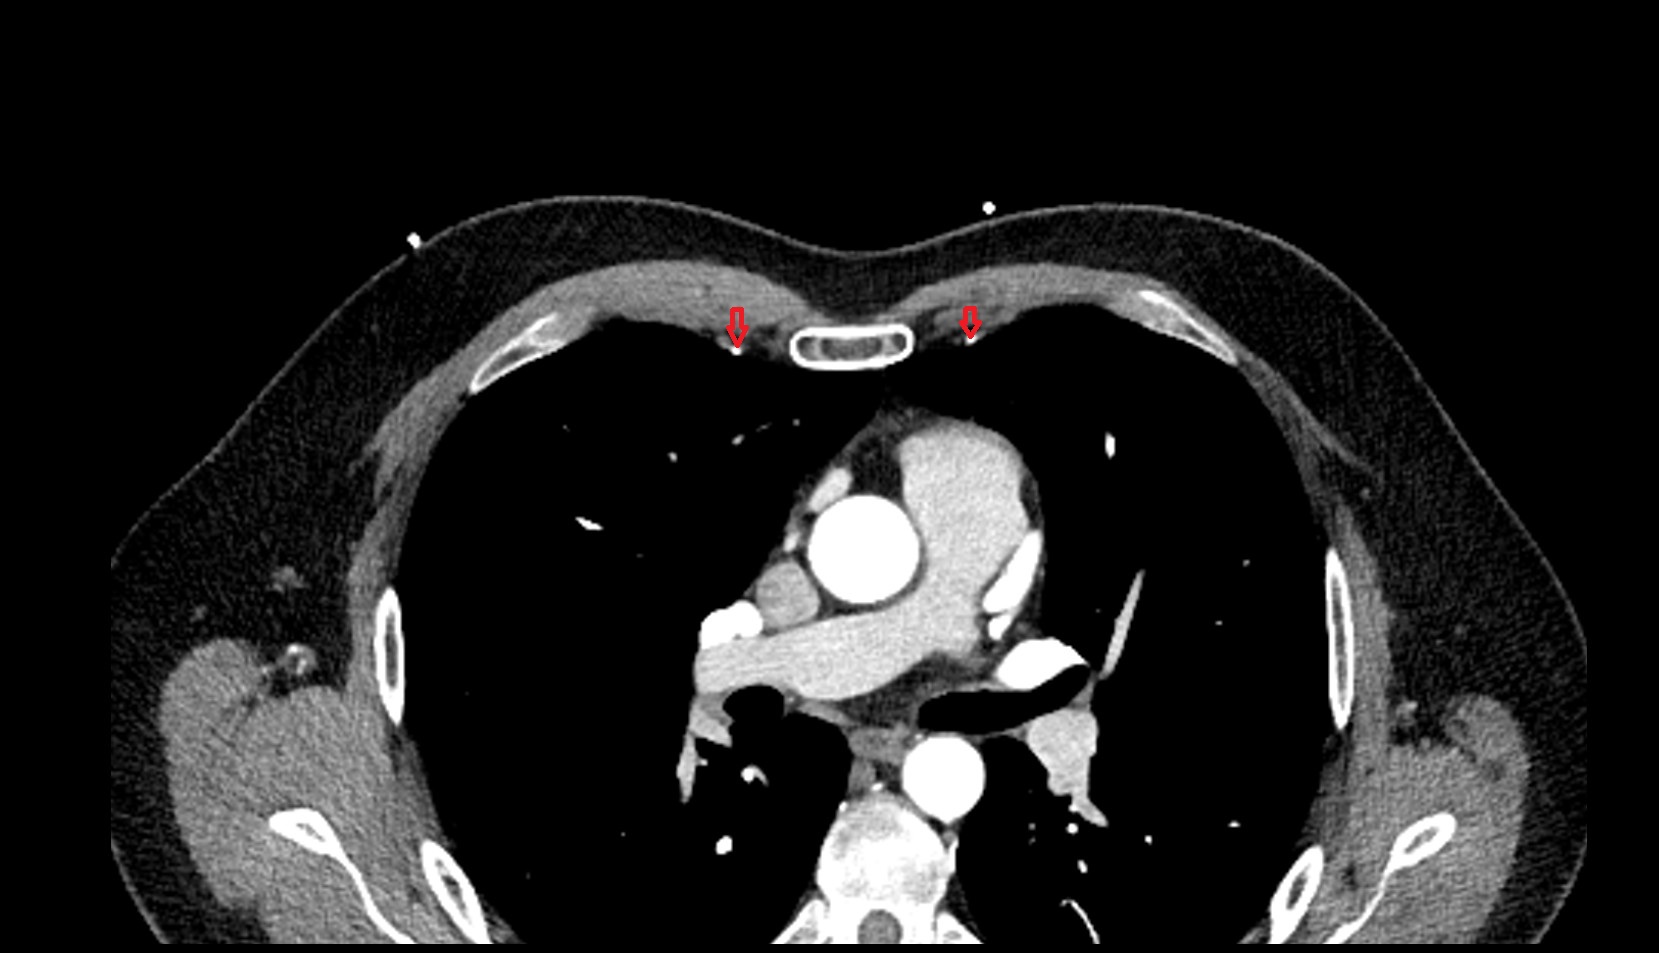

- Thymus